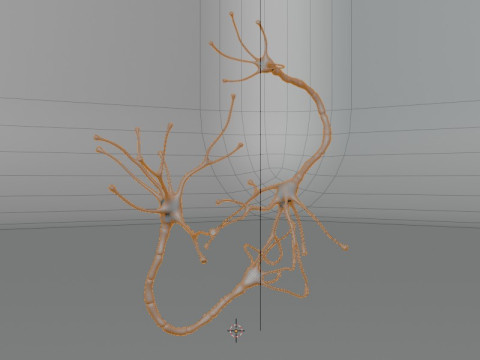

Neuron Sel Saraf Realistis Low-poly Model 3D

Neuron Sel Saraf Realistis Model 3D blend, png, Dari 3dcreations

A highly detailed and realistic 3D model of a human nerve cell (neuron), showcasing dendrites, axon, and synaptic terminals with scientific accuracy. Perfect for anatomy study, educational visualization, and medical simulations.

⚙️ Key Features:

Realistic and scientifically accurate nerve structure

Includes detailed axon, dendrites, and cell body

Ideal for educational and medical 3D projects

Smooth mesh topology for easy rendering and animation

Suitable for VR, AR, and scientific visualization

High-quality texture and proportionally accurate modeling